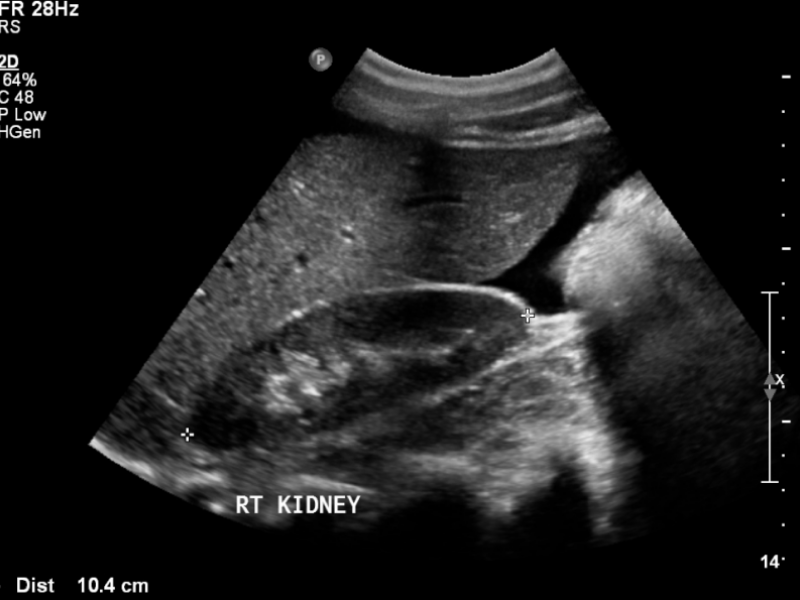

A 17-year-old female presents to your ED with abdominal pain